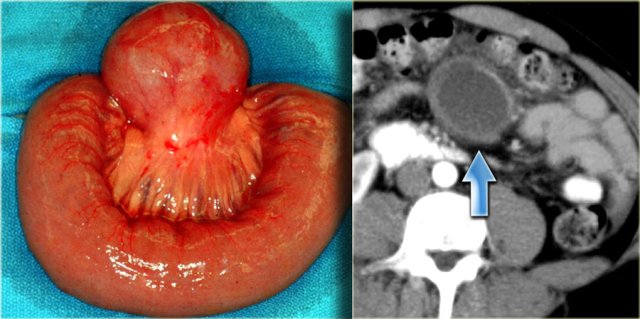

The case on the left is also a lymphangioma.

Notice that CT does not always appreciate the septations, although the specimen clearly shows multiple septations.

Ultrasound or MR depict these septations better than CT.

On the left an enteric duplication cyst.

It is located in the transverse mesocolon.

This patient was suspected of having a cystic pancreatic tumor.

The specimen demonstrates all the bowel wall layers.